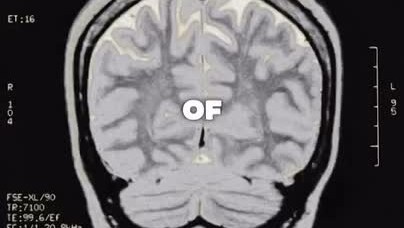

Диссоциальное расстройство личности - что это и как проявляется.